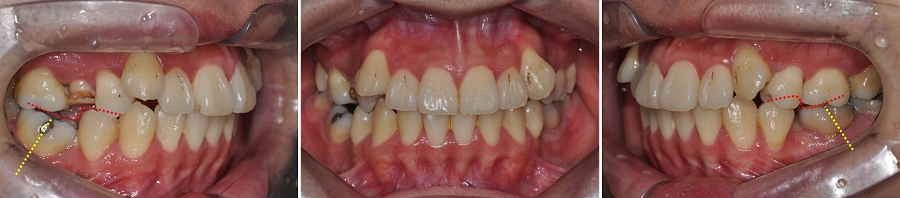

복잡도가 높았던 초진상태

이번 환자분은 처음 내원하셨을 때부터 여러 치아 문제들이 동시에 존재하는 케이스였습니다.

단순 배열 문제가 아니라, 치아 결손·치아 경사·대구치 전방이동· 송곳니 덧니·치아 파절·충치 다수·심미적 문제가 한꺼번에 얽혀 있었죠.

✔ 초진 특징 요약

• 골격성 2급 부정교합

• 상악 우측 제2소구치 : 신경치료 후 크라운 수복을 미루다가 치아 파절

• 상악 좌측 제2소구치 결손 → 좌측 상악 대구치들의 전방이동

• 상악 양측 견치 공간 부족 → 높은 위치(High Canine)

• 하악 제2소구치 양측 모두 심한 설측경사

→ 그 공간으로 제1대구치가 전방 쓰러져 제2소구치의 공간이 거의 없는 상태

• 구강 내 충치 및 수복 필요 치아 다수

• 상악 전치부 순면 변연융선이 과도하게 발달 → 심미적 문제 + 브라켓 부착 어려움

치료 전에 어디부터 손대야 할지 정확한 구조 분석이 필수인 케이스였습니다.